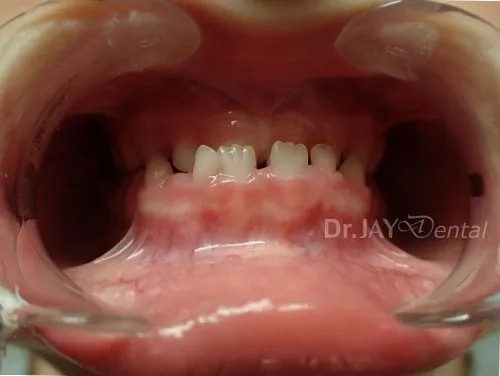

CASE 4

Early intervention plays a big role, the kid was 7yrs old, we started treating her early, helped facilitate her growth and wider palate helping her sleep better as she had good airway. Patient was having night terrors and sleep disturbances along with snoring. The treatment change was in 4 months.